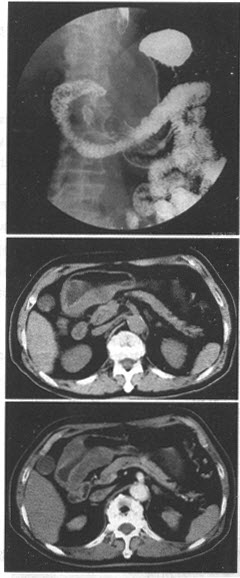

患者,女,57岁。上腹疼痛,不易缓解,吐咖啡色血液。上消化道造影检查示,胃窦部胃壁运动僵硬。行上消化道钡餐CT检查,如图。